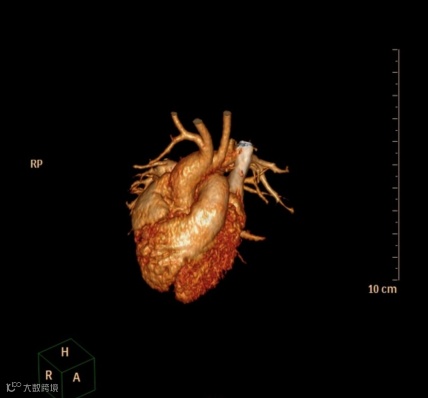

患儿,女,3月龄,出现喘息和喂养困难,肺动脉吊带,右位心。

轴位MIP图像显示心尖指向右侧,异常的左肺动脉(肺动脉吊带)起源于右肺动脉,穿过气管和食管之间,在气管远端分叉处导致管腔轻度狭窄,并压迫右主支气管使其近端狭窄,从而引起上呼吸道症状。